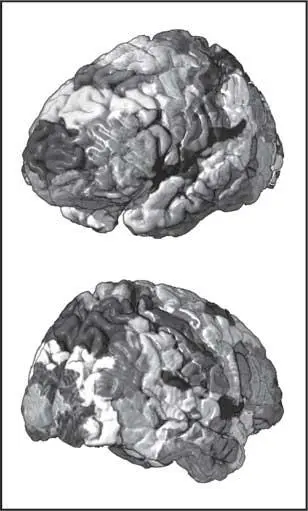

Рис. 38. Поля Бродмана, нанесенные на поверхность коры мозга